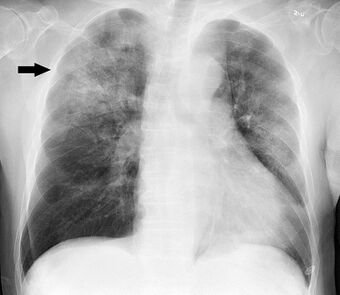

| Chest X-ray of a pneumonia caused by influenza and Haemophilus influenzae, with patchy consolidations, mainly in the right upper lobe (arrow) | |

Most bacteria enter the lungs via small aspirations of organisms residing in the throat or nose.[24] Half of normal people have these small aspirations during sleep.[28] While the throat always contains bacteria, potentially infectious ones reside there only at certain times and under certain conditions.[28] A minority of types of bacteria such as Mycobacterium tuberculosis and Legionella pneumophila reach the lungs via contaminated airborne droplets.[24] Bacteria can also spread via the blood.[25] Once in the lungs, bacteria may invade the spaces between cells and between alveoli, where the macrophages and neutrophils (defensive white blood cells) attempt to inactivate the bacteria.[56] The neutrophils also release cytokines, causing a general activation of the immune system.[57] This leads to the fever, chills, and fatigue common in bacterial pneumonia.[57] The neutrophils, bacteria, and fluid from surrounding blood vessels fill the alveoli, resulting in the consolidation seen on chest X-ray.[58]

A chest radiograph is frequently used in diagnosis.[23] In people with mild disease, imaging is needed only in those with potential complications, those not having improved with treatment, or those in which the cause is uncertain.[23][67] If a person is sufficiently sick to require hospitalization, a chest radiograph is recommended.[67] Findings do not always match the severity of disease and do not reliably separate between bacterial and viral infection.[23]

X-ray presentations of pneumonia may be classified as lobar pneumonia, bronchopneumonia, lobular pneumonia, and interstitial pneumonia.[73] Bacterial, community-acquired pneumonia classically show lung consolidation of one lung segmental lobe, which is known as lobar pneumonia.[41] However, findings may vary, and other patterns are common in other types of pneumonia.[41] Aspiration pneumonia may present with bilateral opacities primarily in the bases of the lungs and on the right side.[41] Radiographs of viral pneumonia may appear normal, appear hyper-inflated, have bilateral patchy areas, or present similar to bacterial pneumonia with lobar consolidation.[41] Radiologic findings may not be present in the early stages of the disease, especially in the presence of dehydration, or may be difficult to interpret in the obese or those with a history of lung disease.[24] Complications such as pleural effusion may also be found on chest radiographs. Laterolateral chest radiographs can increase the diagnostic accuracy of lung consolidation and pleural effusion.[40]